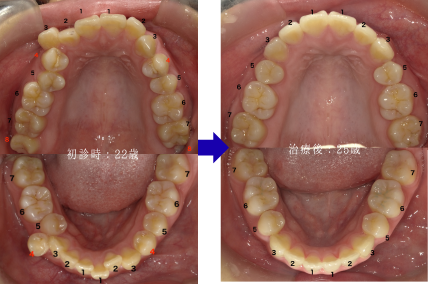

【抜歯位置・本数について】

歯を移動させるスペースが不足したため、赤字の箇所(上下左右4番・上下左右8番:合計8本 )を抜歯しました。※下顎左右8番は萌出前に抜歯しました。